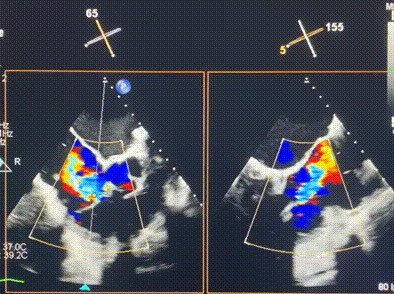

術(shù)后DSA顯示Lux-Valve Plus與Tendyne和ICD無相互影響

術(shù)后超聲顯示僅殘余微量瓣周漏

LuX-Valve Plus經(jīng)血管三尖瓣置換系統(tǒng)此次“出海”圓滿完成,術(shù)后Rodrigo Estévez-Loureiro教授對LuX-Valve Plus經(jīng)血管三尖瓣置換系統(tǒng)的器械性能和治療效果大為稱贊,認為LuX-Valve Plus的手術(shù)體驗非常好。術(shù)后即刻超聲顯示三尖瓣反流幾乎完全消失,血流動力學(xué)改善顯著,患者恢復(fù)快。在面對復(fù)雜解剖結(jié)構(gòu)、超聲影像質(zhì)量不佳、有起搏導(dǎo)線干擾時,Lux-Valve Plus也體現(xiàn)了極強的適應(yīng)性。Thomas Modine教授和Anson Cheung教授也肯定了LuX-Valve Plus術(shù)中操作的便捷性,認為LuX-Valve Plus容錯率高,對術(shù)中影像的依賴較小,后期希望可以更多的應(yīng)用LuX-Valve Plus三尖瓣置換系統(tǒng)于臨床實踐,讓更多的三尖瓣重度反流患者盡早獲益,改善預(yù)后。